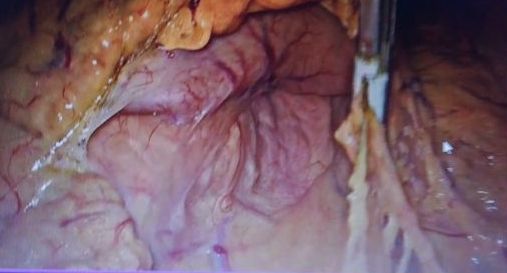

诊断:1.胃癌,性质待病理;病理活检,胃镜病理示:(胃体)粘膜轻度慢性炎,中度萎缩,部分腺体高度异型增生,局部呈腺癌改变。处理:完善辅检后行腹腔镜胃癌根治术,术中注意肝十二指韧带及脾门区血管解剖,这样才不会导致术中操作不当的出血。遵循正确的手术方法。遵循术中清扫步骤,首先要暴露脾门区,其次裸化胃网膜左血管和裸化脾动脉,最后裸化脾叶动脉。处理好术后的并发症。肝十二肠韧带及脾门淋巴结清扫最容易发生的并发症是引起血管的损伤,脾被膜的损伤,引起出血,术中控制不了出血的话只能进行脾切除,本例手术顺利。术后胃肠外营养,抗感染,补液。术后7天治愈出院。